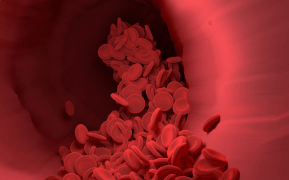

고지혈증은 혈중 콜레스테롤 또는 중성지방 수치가 정상보다 높은 상태를 말합니다.

심근경색, 뇌졸중 등 심혈관 질환 위험 증가

혈관은 한 번 막히면 되돌리기 어렵습니다.